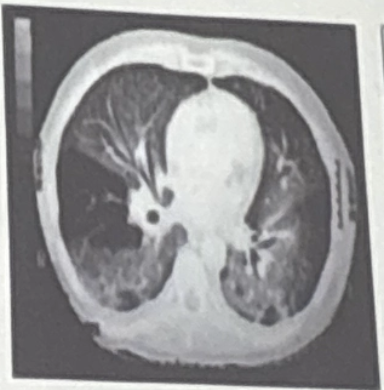

¿Qué patrón tomográfico corresponde a NOC?

A

• Consolidaciones

• lob superiores

• halo invertido

¿Cuáles son patrones de disminución de atenuación?

• Panal de abeja

• Quistes

• Enfisema

• Bronquiectasias

• Bulas

• Cavitaciones